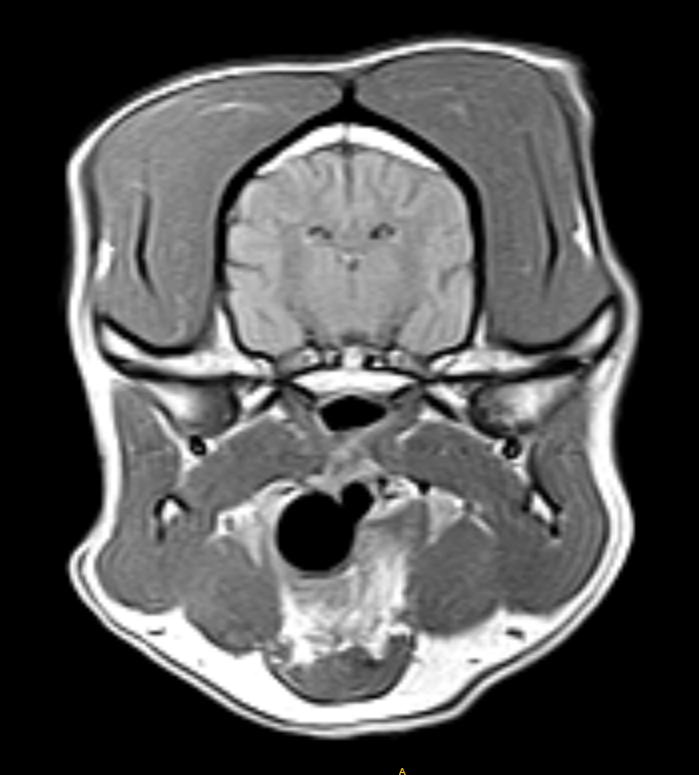

Imágenes de Calidad Premium

VET MR GRANDE

IMÁGENES CLÍNICAS

En la sección de imágenes clínicas, destacamos la precisión y claridad de nuestros estudios, respaldados por un equipo de radiólogos especializados en medicina veterinaria. Nos enorgullece ser un aliado confiable para veterinarios y clínicas, brindando un servicio rápido y eficiente para ayudar en la toma de decisiones clínicas fundamentadas.

Utilizamos resonancia magnética para obtener imágenes detalladas de tejidos blandos, articulaciones y el sistema nervioso central, permitiendo diagnósticos más precisos.